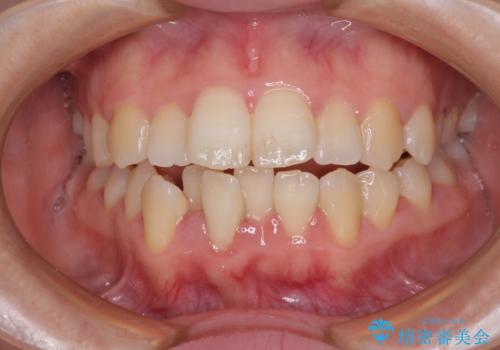

[ 前歯開咬 ] 前歯が噛んでいない マウスピース矯正治療

担当医 大元洋佑